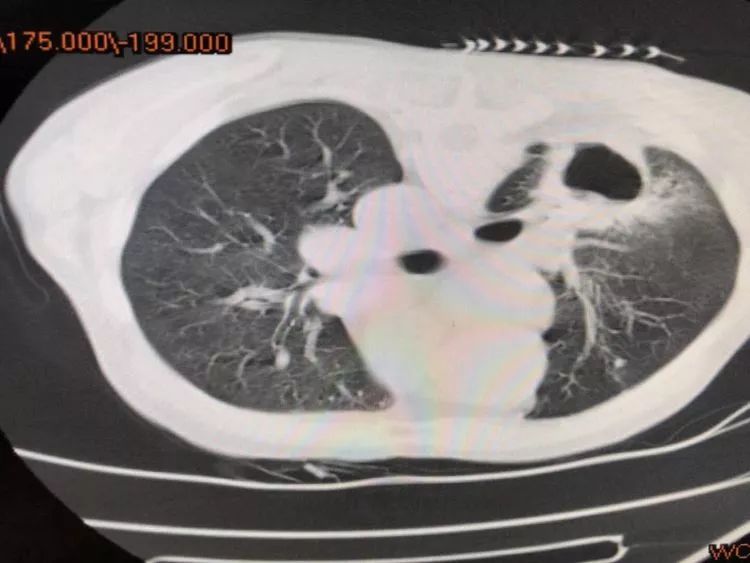

第一例 79歲的陳爺爺來省胸科醫(yī)院就診,經(jīng)檢查胸部CT厚壁空洞,氣管鏡檢查提示外壓性狹窄,為明確診斷,肺穿刺是最佳選擇,通過CT引導,洞壁取材。

從影像學上考慮腫瘤的可能性更大,一般空洞我們多考慮鱗癌,可是,病理報告告訴我們,腺癌也可以形成大空洞,同時患者椎體MRI提示骨轉移,錯失最佳治療時機。